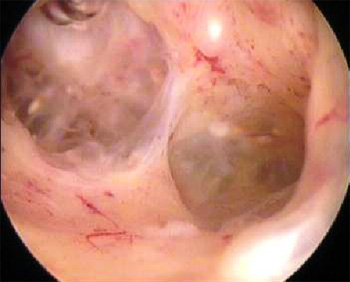

Hysteroskopische Polypenentfernung

Gebärmutterpolypen sind meistens gutartige Veränderungen der Schleimhaut der Gebärmutter. In manchen Fällen führen diese zu Schmerzen und Blutungsstörungen.

In diesen Fällen benutzen wir ein Resektoskop, ein spezielles chirurgisches Instrument, mit dem unter optischer Kontrolle die Polypen mit einer kleinen Schlinge durch den Gebärmutterhals abgetragen werden.